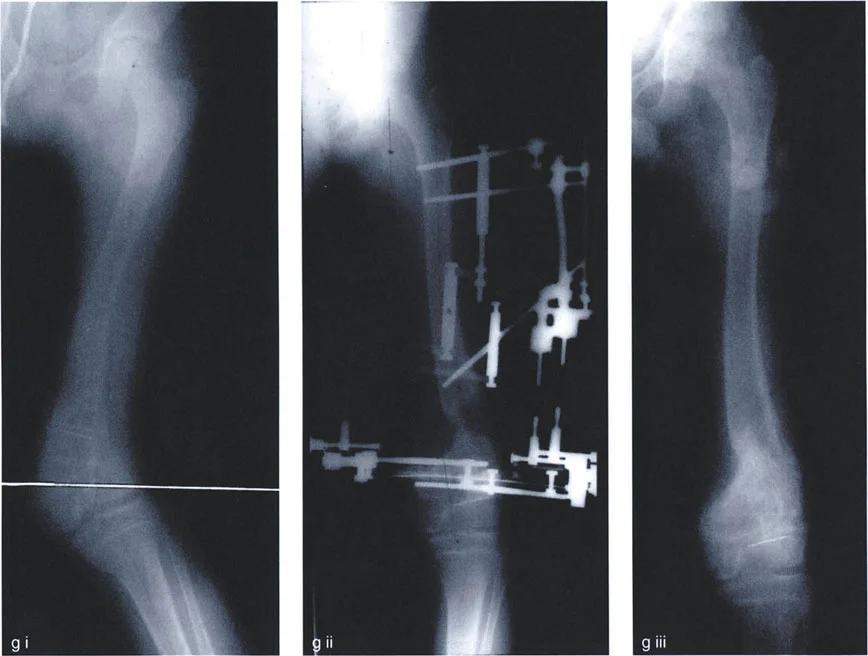

Step by Step Guide to Frontal Plane Deformity Planning

Mastering Paley's principles requires a systematic approach to preoperative planning. Skipping steps or relying on intraoperative "eyeballing" guarantees failure.

Preoperative Radiographic Assessment

- Obtain Proper Imaging The foundation of planning is a high-quality, standing, full-length AP radiograph of both lower extremities.

- Patella Forward Positioning The radiograph must be taken with the patella facing strictly forward, regardless of foot position. This isolates the frontal plane deformity from any rotational deformity.

- Calibrate the Image Ensure the digital radiograph is calibrated using a scaling marker to allow for accurate millimeter measurements.

Executing the Preoperative Plan

- Perform the Malalignment Test Draw the mechanical axis from the center of the femoral head to the center of the ankle. Measure the MAD. Determine if the mechanical axis falls in the medial, lateral, or central zone of the knee.

- Perform the Malorientation Test Draw the individual mechanical axes of the femur and tibia. Measure the mLDFA, MPTA, LPFA, and mLDTA. Compare these to normal values to isolate the source bone of the deformity.

- Locate the CORA Draw the Proximal Mechanical Axis (PMA) and Distal Mechanical Axis (DMA) using the normal joint orientation angles. Mark their intersection as the CORA.

- Select the Osteotomy Rule Determine if the bone can be safely cut at the CORA (Rule 1) or if the cut must be moved to the metaphysis (Rule 2).

- Choose the Osteotomy Sequence Decide between an opening wedge, closing wedge, or dome based on limb length discrepancy and soft tissue constraints.

- Simulate the Correction Using digital templating software, digitally cut the bone, place the ACA, and rotate the segment. Verify that the final mechanical axis passes through the center of the knee and that joint lines are parallel to the floor.

Advanced Clinical Applications and Surgical Pearls

Applying these geometric concepts in the operating room requires bridging the gap between mathematical theory and biological reality.

Juxta Articular Deformities

Deformities located very close to the joint line present a unique challenge. The CORA is often located within the epiphysis or the joint space itself.

- Surgical Pearl You cannot cut through the CORA in these cases. You must utilize Paley's Rule 2. Place your hinge (ACA) at the joint line (the CORA), and perform your osteotomy in the metaphyseal bone.

- Managing Translation Be prepared for the resulting translation. When using a plate for fixation, you may need to use a specialized offset plate or manually contour the plate to accommodate the step-off. If using an intramedullary nail, blocking screws (Poller screws) are essential to guide the nail and maintain the translation without allowing the bone to slide back into deformity.

Diaphyseal Deformities

Midshaft deformities are typically the most straightforward to plan but can be challenging to fixate if the bone quality is poor.

* Surgical Pearl Always aim for Rule 1. Cut exactly at the CORA. This allows for the use of an intramedullary nail, which provides load-sharing biomechanics and allows for early weight-bearing.

* Beware the Sagittal Plane Diaphyseal deformities rarely exist purely in the frontal plane. Always evaluate the lateral radiograph for procurvatum or recurvatum and plan for a multi-planar correction.